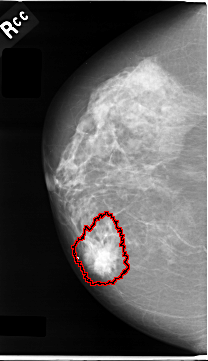

C_0006_1.RIGHT_CC

FILE: C_0006_1.RIGHT_CC.OVERLAY

TOTAL_ABNORMALITIES 1

ABNORMALITY 1

LESION_TYPE MASS SHAPE IRREGULAR MARGINS SPICULATED

ASSESSMENT 5

SUBTLETY 5

PATHOLOGY MALIGNANT

TOTAL_OUTLINES 1

BOUNDARY